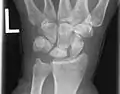

Shown is the right hand, palm down (left) and palm up (right).

Proximal: A=Scaphoid, B=Lunate, C=Triquetral, D=Pisiform

Distal: E=Trapezium, F=Trapezoid, G=Capitate, H=Hamate